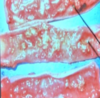

AVIAN COCCIDIA

Schizonts full of

trophozoites or merozoites

Schizonts full of trophozoites or merozoites

AVIAN COCCIDIA

Schizonts full of trophozoites or merozoites